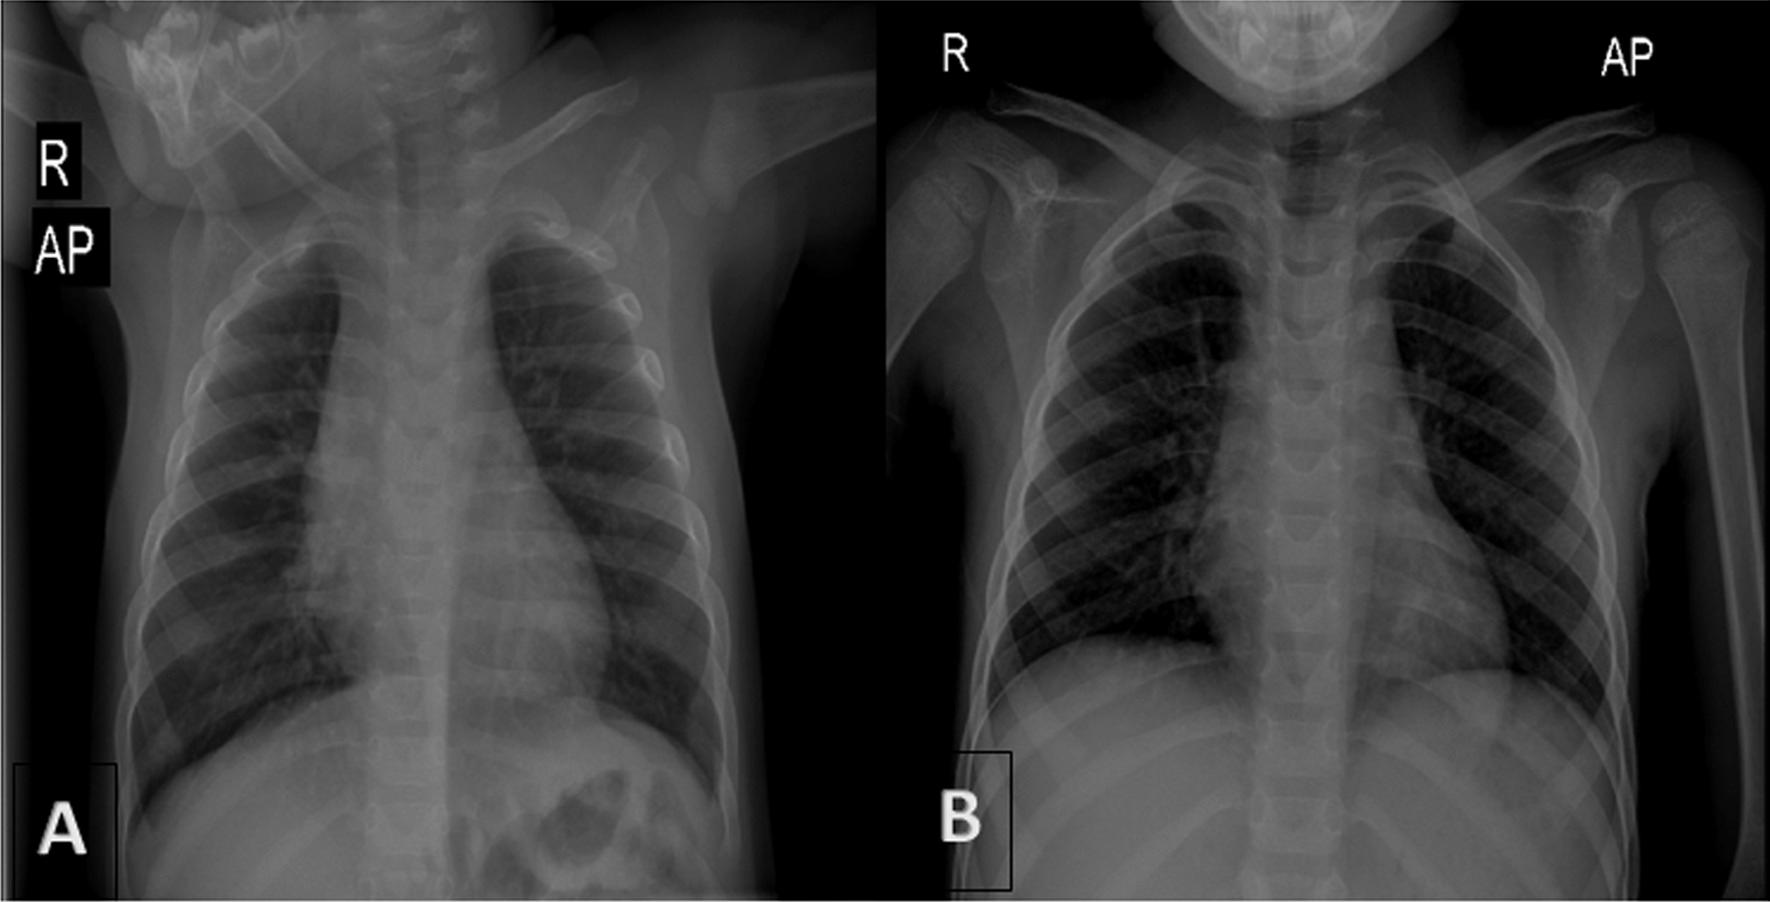

A 9-year-old persian boy was referred with complaint of intermittent abdominal pain in the left lower quadrant and an episode of vomiting. The patient was tachypneic, and the abdomen was nontender on examination. Lung sounds on the left side were considerably decreased, whereas heart sounds on the right side were louder. There was no history of underlying disease in the patient. Initial laboratory blood tests, chest x-ray, spiral computed tomography scan, and chest sonography were requested. Blood tests were normal, and chest x-ray revealed a round-shaped lesion with relatively clear boundaries containing air-fluid level and shift of the heart and mediastinum to the right. A spiral computed tomography scan of the lungs demonstrated the shift of the heart and mediastinum to the right side was due to dilated stomach and colon pressure, and chest sonography revealed that half of the stomach was inside the thorax. Laparotomy surgery was performed. The patient had no complications following surgery.

一名 9 岁的波斯男孩因左侧下腹部间歇性疼痛和呕吐就诊。患者呼吸急促,腹部检查无压痛。左侧肺部听诊明显减弱,而右侧心音增强。患者无潜在疾病史。最初要求进行实验室血液检查、胸部 X 射线检查、螺旋 CT 扫描和胸部超声检查。血液检查正常,胸部 X 射线显示圆形病变,边界相对清晰,内含气液平面,伴有心脏和纵隔向右侧移位。肺部螺旋 CT 扫描显示心脏和纵隔向右侧移位是由于扩张的胃和结肠压力所致,胸部超声显示一半的胃在胸腔内。行剖腹手术。术后患者无并发症。